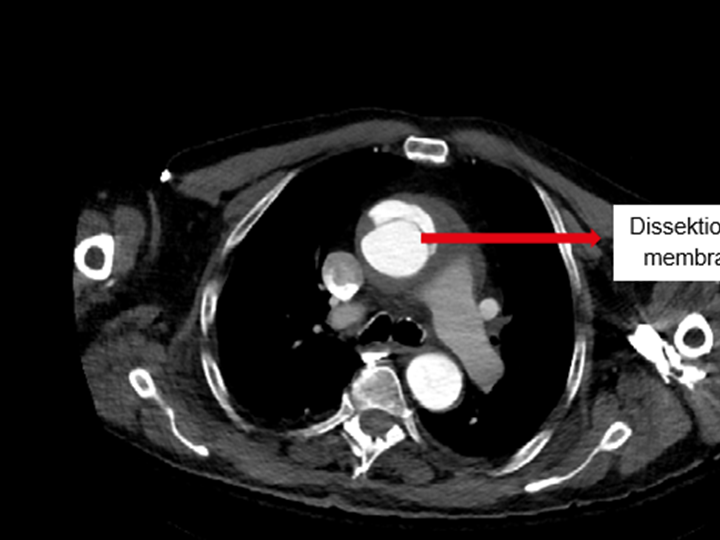

Die Verdachtsdiagnose erhärtet sich und nach (schwieriger) Stabilisierung mit Norboli und mittlerweile auch Supraboli (jeweils 1:100) wird unter Spontanatmung ein CT Thorax und Abdomen angefertigt. Das CT muss mehrmals aufgrund der zunehmenden Instabilität (RR bis 35syst mit Nor- und SupraBoli max 80syst.) unterbrochen werden. Die Anfertigung gelingt und im CT bestätigt sich eine ausgeprägte Typ A- Dissektion der Aorta.

Im Rahmen der Diagnosefindung bestätigte sich die Aortendissektion (Typ A).

Info: Unter einer Aortendissektion (Riss der Hauptschlagader) versteht man den Einriss der inneren Schicht der Aorta, wodurch Blut in die Wandschichten eindringt und diese aufspaltet. Die akute Typ A-Dissektion - bei welcher die Einblutung bereits im aufsteigenden Anteil der Aorta beginnt und sich so über die gesamte Länge ausbreiten kann - ist ein lebensbedrohlicher Notfall und bedarf einer sofortigen operativen, herzchirurgischen Versorgung.